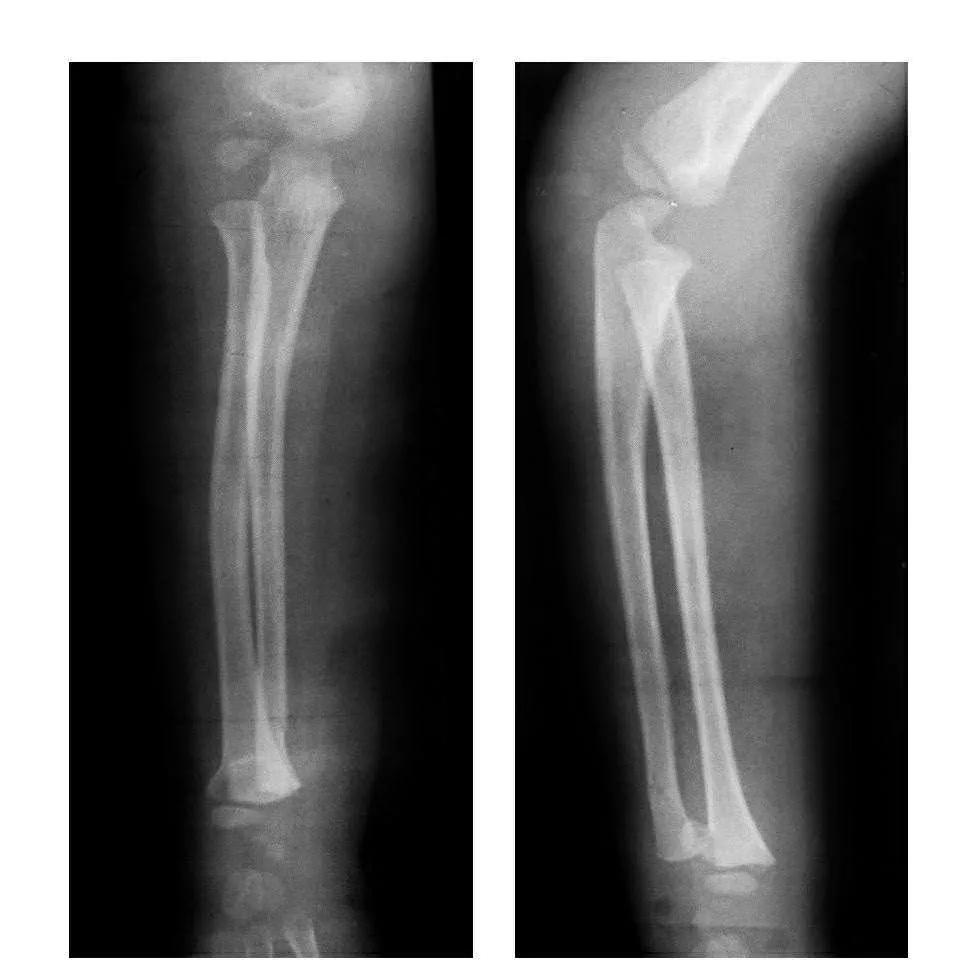

例6:肱骨外髁骨折合并桡骨远端骨骺滑脱并尺骨下段骨折。